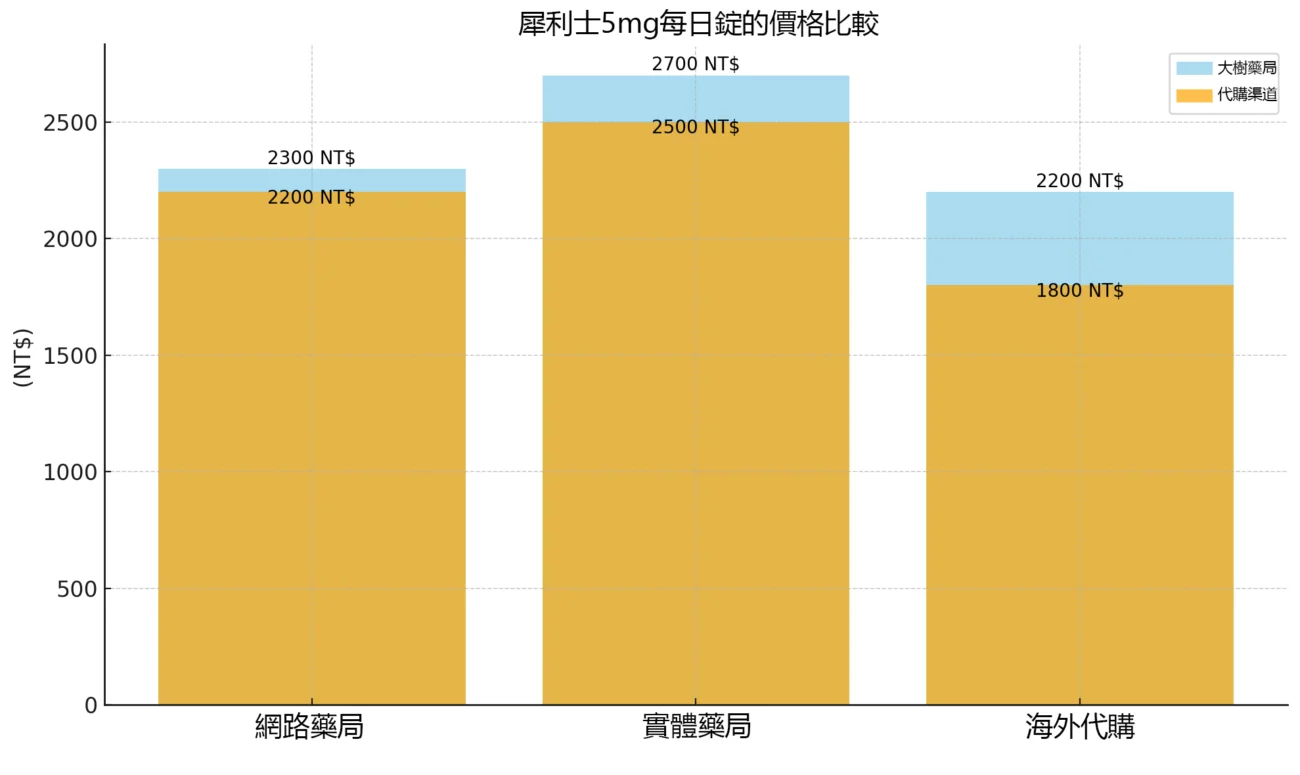

四、犀利士5mg價格比較

購買犀利士5mg每日錠的價格會根據購買渠道、包裝規格和劑量而有所變動。以下是一些常見的價格範圍供您參考:

- 網路藥局:價格大約在 NT$1600 至 NT$1800 之間,具體價格取決於購買的數量和包裝規格。

- 實體藥局:價格通常會稍高於網路藥局,大約在 NT$1700 至 NT$2000 之間,購買時需出示處方箋。

- 海外代購:價格相對較低,但需要支付運費和等待時間,大約在 NT$1200 至 NT$1500 左右。